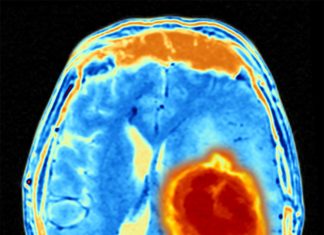

„Evrica!”: Scanările cerebrale dezvăluie ce se întâmplă în minte atunci când...